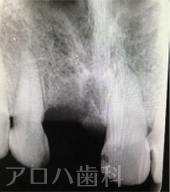

CASE01/60代女性

初診時

| 主訴 | 左の前歯が折れた |

| 治療内容 | 左上前歯にお痛みがあり、土台を外したところ、破折により抜歯となった方です。 骨が薄かったため、抜歯と同時にインプラントを行う【抜歯即時インプラント】を行いました。 インプラント治療により歯があったときと変わらない状態に回復しました。 |

| 治療期間 | 1週間 |

| 治療費用 | 627,000円 |

| 費用詳細 | ・TEC 22,000円 ・サージカルガイド 55,000円 ・GBR 110,000円 ・インプラント手術+アバットメント+上部構造 440,000円 |